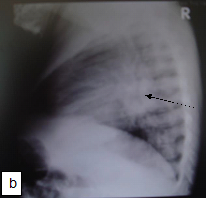

Chest X-ray (CXR): TB enlarged perihilar lymph nodes are better visualised on a lateral CXR than a PA view, therefore, it is important to obtain both PA and lateral films when evaluating a child with suspected TB.